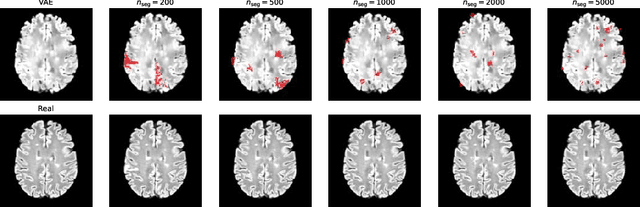

Abstract:Segmentation of cerebral blood vessels from Magnetic Resonance Imaging (MRI) is an open problem that could be solved with deep learning (DL). However, annotated data for training is often scarce. Due to the absence of open-source tools, we aim to develop a classical segmentation method that generates vessel ground truth from Magnetic Resonance Angiography for DL training of segmentation across a variety of modalities. The method combines size-specific Hessian filters, hysteresis thresholding and connected component correction. The optimal choice of processing steps was evaluated with a blinded scoring by a clinician using 24 3D images. The results show that all method steps are necessary to produce the highest (14.2/15) vessel segmentation quality score. Omitting the connected component correction caused the largest quality loss. The method, which is available on GitHub, can be used to train DL models for vessel segmentation.